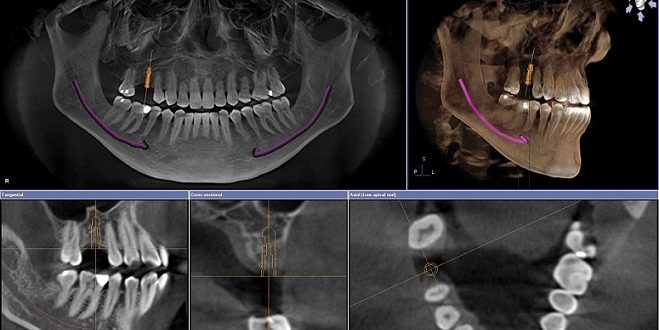

GUÍAS PARA CIRUGÍA

Se realiza con la tomografía planeando el sitio en donde se va a colocar el implante de tal manera que este dispositivo nos permite colocar los implantes de forma segura en la misma posición que queda en el computador.